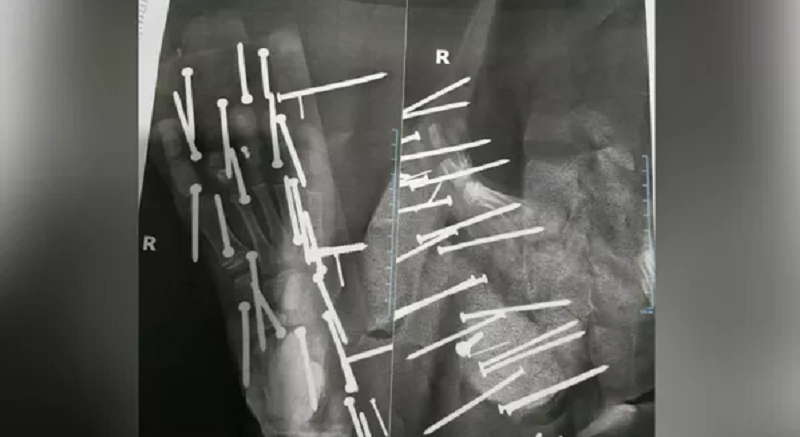

Mais de 28 perfurações foram identificadas no pé da criança — Foto: Reprodução/Redes Sociais

No raio-x que circulou nas redes sociais é possível perceber que o pé do garoto teve no mínimo 28 perfurações de pregos e parafusos. O menino teve que passar por um procedimento cirúrgico.

Apesar do susto, a criança passa bem, mas o procedimento foi delicado, para não comprometer o movimento do pé da criança e evitar sequeças. O menino recebeu alta na sexta-feira (7).